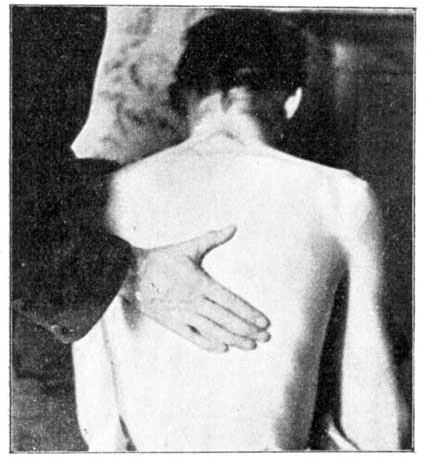

Ankle Swelling.—When long continued in connection with disease or accident, this sometimes leads to a partial withering of the limb up to its very root. In such a case it is best to deal first with the roots of those nerves which supply the limb, which are, in the case of the legs, in the lower part of the back. It is important to apply light pressure to these roots by gently squeezing the muscles of the lower back. This raises a feeling of gentle heat, which slowly passes down the limbs even to the toes. Then the gentle pressure and squeezing must be carried all down the limb, avoiding any degree of pain, until all its muscles have had their share. While progressing down the limb with his rubbing, let the rubber be careful that the individual strokes of his hands be upwards, towards the hip. The blood will thus be propelled towards the heart, while the stimulus of rubbing is conveyed along the nerve trunks towards the foot. The squeezing should be done with a grasping movement of the hands, the limb being held encircled in both hands, thumbs upwards. Warm olive oil is used in this squeezing, and also, if the skin be hard and dry, soap lather (see Lather).

During all this treatment the whole back should be gently rubbed daily with warm olive oil for half an hour, if as much can be borne.

Treatment may also be given for lack of assimilative power. The back, especially on either side of the spine, is rubbed with gentle pressure and hot olive oil. This pressure is so applied that a genial heat arises along the whole spinal column. This done twice a day, for half-an-hour at a time, and continued for several weeks, will markedly restore assimilative power. Cases which have been perfectly helpless for eight and even ten years are cured by this simple method, sufficiently and carefully followed.

We had a patient who was stout, but weak and weary, with the muscles slack and showing loss of power. The effect of back-rubbing, accompanied by easily assimilated food in small quantities and often, was to lessen his weight by a considerable amount. But the muscular power at once began to increase, and the man was soon like one made anew. Digestion had not been impaired in this case, but the blood formed by it was not converted into good living substance. Sight and hearing have even been restored by these means when the failure in eye or ear has been due to waste material accumulating, as frequently is the case.

In connection with many troubles, what may be called local assimilation has to be considered. A foot, say, with a bad abscess or diseased bone (see Pain, Severe) is cured by hot bathing and pressure. From a shrunken and feeble limb, the leg grows to a healthy and strong one. This occurs because the heat and pressure have so stimulated its vitality that the material supplied by the blood can be utilised in the leg for purposes of healthy growth. So with any other part of the body. Such diet as we have indicated supplies easily assimilated substance. The local heating, pressure, and bathing enable this substance to be utilised where it is needed. A little careful thought on this line will guide to proper treatment of almost any case where assimilation has failed, either locally or generally, and will lead the way to a method of cure.